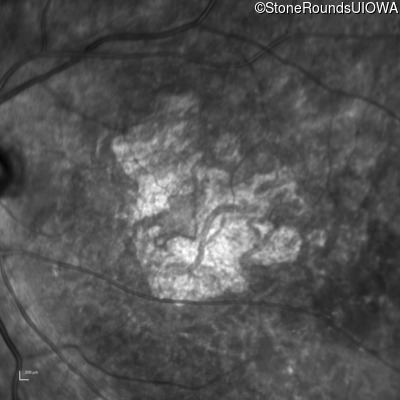

Infrared Fundus Photograph - Right - 20/125 -2

Exemplar